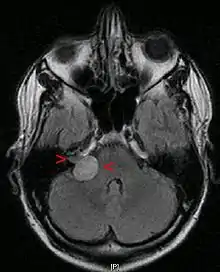

![]() ورم العصب السمعي ثنائي الجانب في مريض يعاني من النوع الثاني من الورم العصبي الليفي ورم العصب السمعي ثنائي الجانب في مريض يعاني من النوع الثاني من الورم العصبي الليفي | |

قد يحدث ورم العصب السمعي لأسباب غير معروفة، ولكن هناك مجموعة متزايدة من الأدلة على أن العيوب الفرادية في الجينات الكابتة للورم قد تؤدي إلى ظهور هذه الأورام عند بعض الأفراد. وذكرت دراسات أخرى التعرض للضوضاء الصاخبة كمسبب للورم. وقد أظهرت إحدى الدراسات وجود علاقة بين ورم العصب السمعي وتعرض الرأس والرقبة للإشعاع، وأيضا وجود تاريخ بالإصابة بورم حميد في الغدد جارات الدرق (ورم قريب من الغدة الدرقية والذي يؤثر على عمليات أيض الكالسيوم). هناك خلافات في ناحية تأثير الترددات الراديوية الصادرة عن الهواتف الخلوية على ظهور الورم، ويبقى هذا الامر مبهما. حتى الآن، لم يثبت علميا بأن العوامل البيئية (مثل الهواتف المحمولة أو النظام الغذائي) تسبب هذه الأورام. جمعية أورام العصب السمعي (ANA) توصي مستخدمي الهاتف الخلوي بكثرة باستخدام السماعات لتمكين فصل الجهاز عن الرأس.[5] على الرغم من أن هناك حالة وراثية تسمى الورم العصبي الليفي من النوع الثاني 2 (NF2) التي يمكن أن تؤدي إلى تشكيل أورام العصب السمعي عند بعض الاشخاص، تحدث معظم اورام العصب السمعي بشكل عفوي دون أي دليل للتاريخ العائلي (95٪).[6] ورم العصبي الليفي يحدث في 1 من 30,000 أو 50,000 ولادة. السمة المميزة لهذا الاضطراب هي ورم ثنائي الجانب في العصبين السمعيين. وهذا يخلق إمكانية الصمم الكامل إذا بقيت الأورام تنمو دون أي ردع. منع أو علاج الصمم الكامل الذي قد يصيب هؤلاء الأفراد يتطلب اتخاذ قرارات معقدة. الاتجاه في معظم المراكز الطبية الأكاديمية في الولايات المتحدة هو علاج الورم الأصغر من الاثنين الذي لديه الفرصة الأفضل للحفاظ على السمع. إذا تم الوصول لهذا الهدف، فيمكن أيضا تقديم العلاج للورم الآخر. إذا لم يتم الحفاظ على السمع في العلاج الأولي، يتم مراقبة الورم الثاني فقط، إذا كان الورم ينمو باستمرار، وأصبح مهددا للحياة، أو في حالة فقدان السمع مع مرور الوقت (بسبب نمو الورم)، يتم البدء بالعلاج. هذه الاستراتيجية لديها أعلى فرصة للحفاظ على السمع لأطول وقت ممكن.